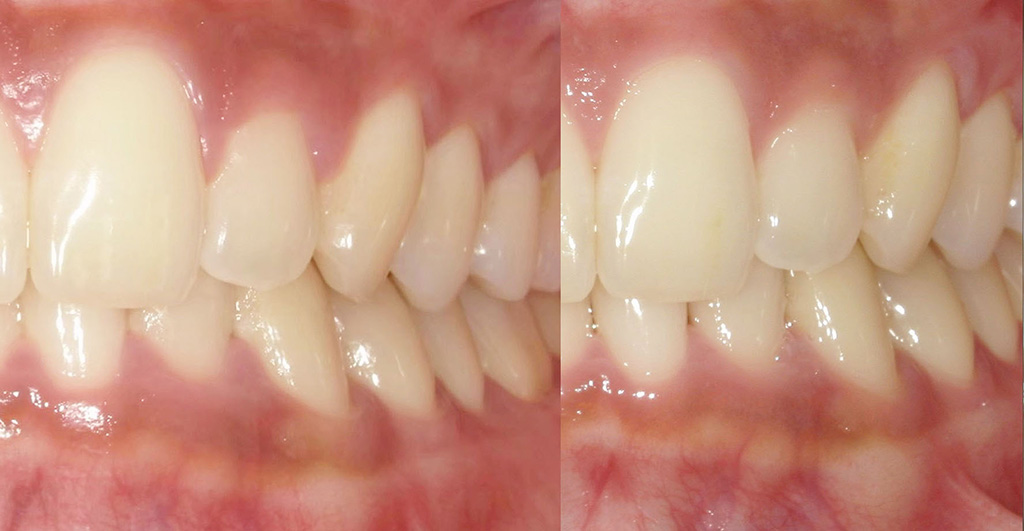

【2ヶ月後】ほぼ毎日フロスしたら…

2ヶ月後、ほぼ毎日フロスを続けた結果を比較してみたのがこちら。

● 歯ぐきの変化

● 清掃状態